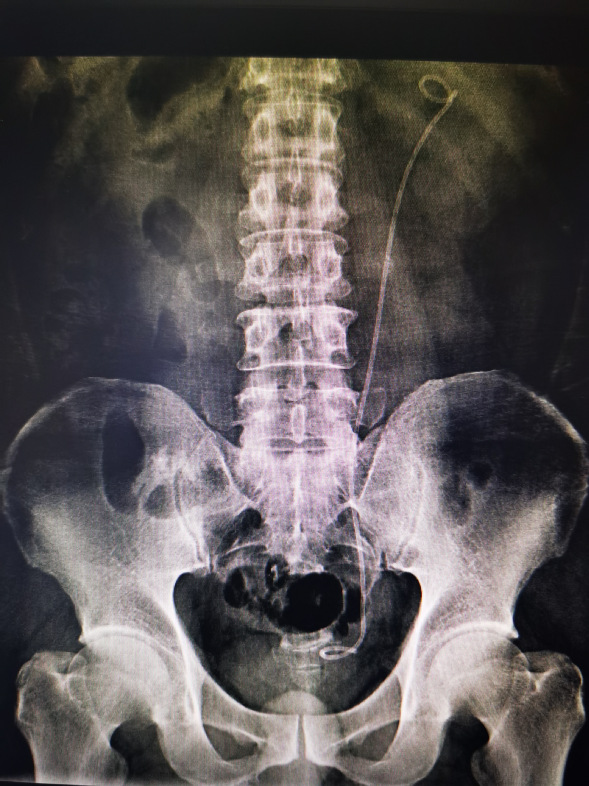

病例二

林先生,诊断:双侧输尿管上段结石并双肾积液。CT检查提示左输尿管上段结石约10*7mm,右输尿管上段结石约13*9mm。

行经尿道输尿管硕通镜下碎石清石术,碎石清石同步,手术高效无创,一次性把两侧结石处理干净,一次手术解决双侧泌尿系梗阻问题,避免造成肾功能衰竭。

手术前

手术后